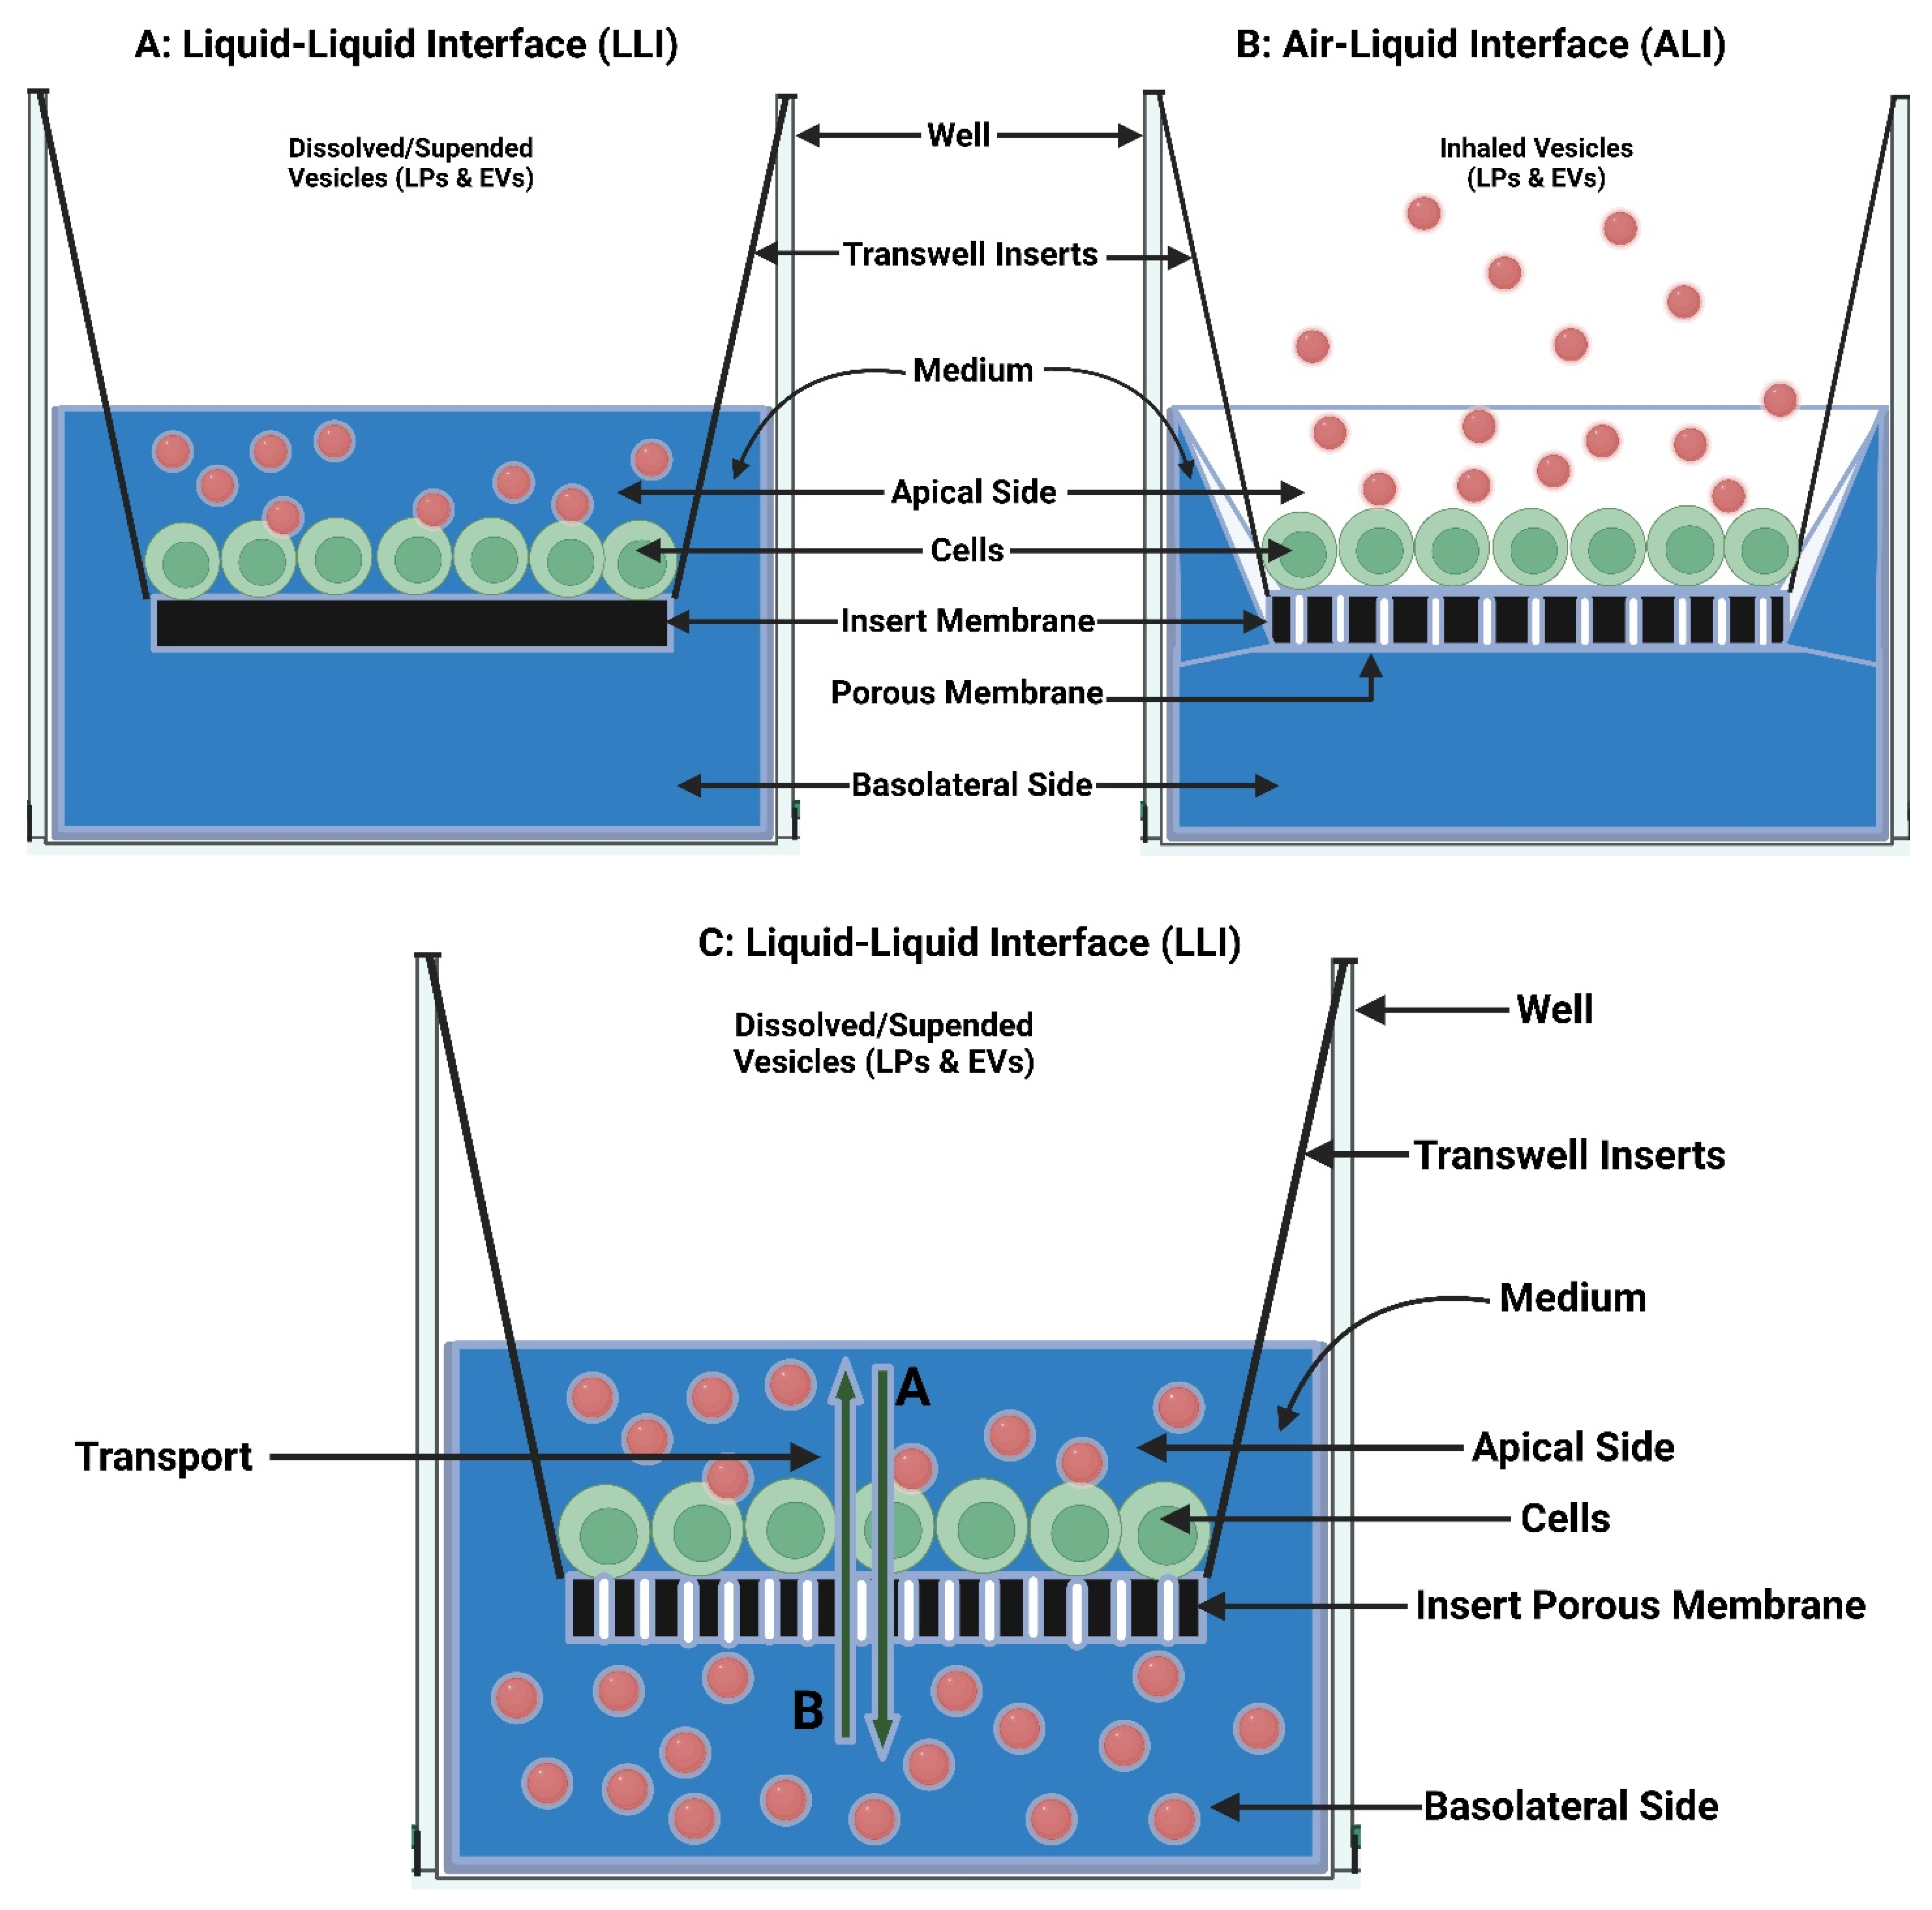

7.1. In Vitro Pulmonary Cell-Based Models